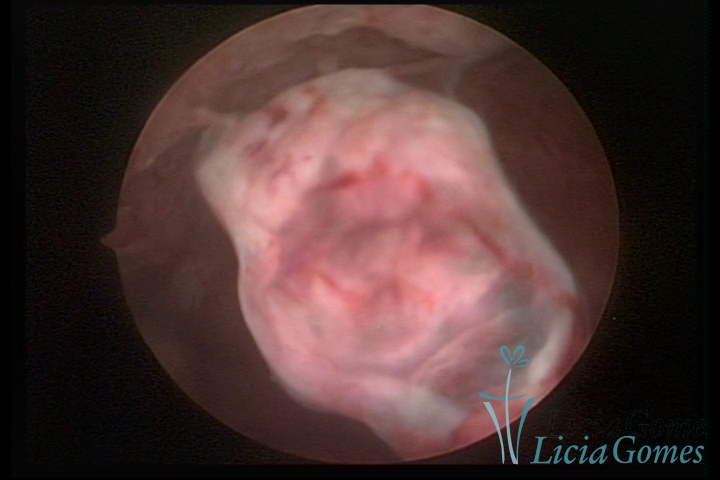

Restos ovulares íntegros em cavidade uterina

×